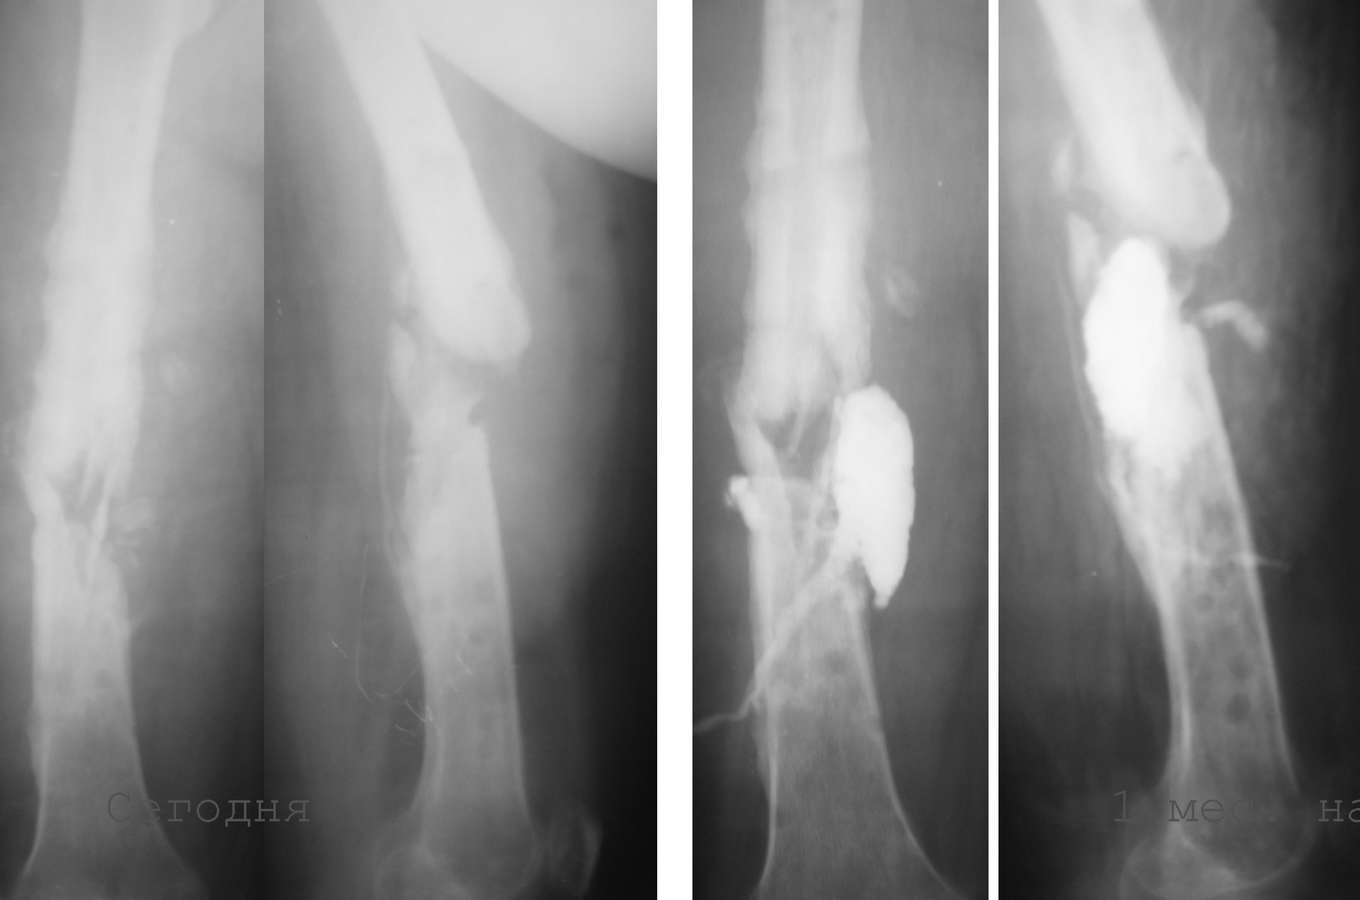

1. 14 мес назад (летом 2008 г)- перелом бедра, оскольчатый, закрытый. Интрамедуллярныйостеосинтез гвоздем Кюнчера, несостоятельная фиксация, поэтому дополнили кокситом.

2. Через 4 мес. ввиду отсутствия перспектив сращения - я выполнил остеосинтез аппаратом Илизарова. В отдельные периоды была надежда наконсолидацию. В аппарате 6-7 мес, постоянные выделения в области стержня - сняли аппарат.

3. 2 мес. ходит с лонгетой, имеется патологическая подвижность. В течение месяца после снятия сохранялись выделения из отверстия, где был стержень, температура до 38, иногда отсутствовала. Сделал фистулу с уверенностью, что это стержневой остеомиелит.

Но контраст ушел в зону перелома, и эвакуировал около 20 мл лизированной крови (без гноя).

хр. остеомиелит, септическое несращение с формированием секвестров бедра - пока инфекция не устранена, сращения не наступит.